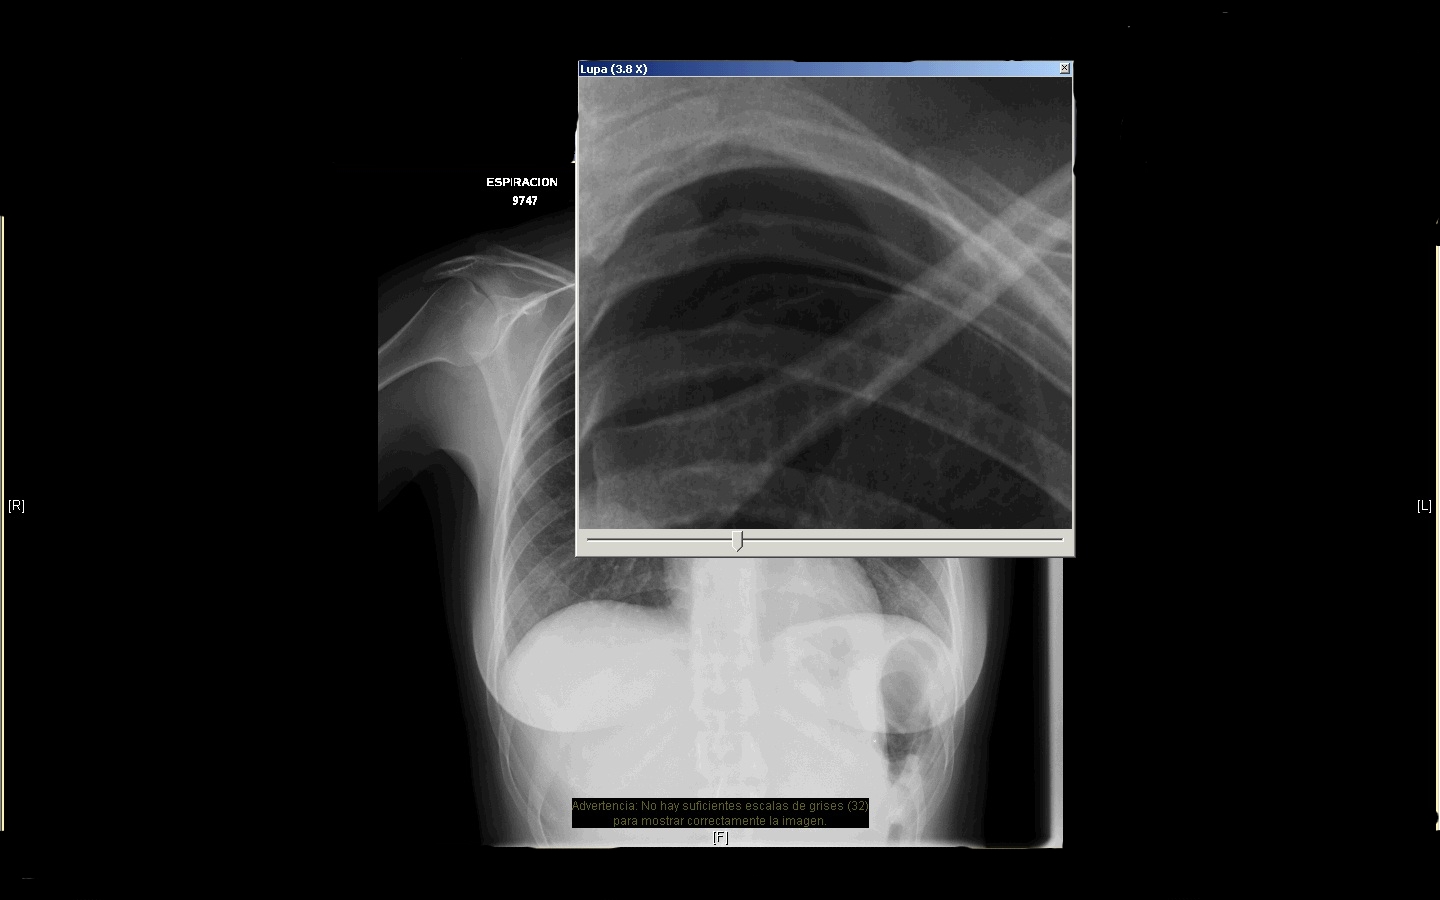

Rx tórax: es la siguiente….

Con lupa enfocada….!!! No se pueden quejar. Os propongo plantear diagnosticos

Mujer de 32 años acude a urgencias del centro de salud porque ayer inició dolor en hemitorax izquierdo al incorporarse de una silla, refiere que el dolor se acentua con los movimientos  y con la inspiración profunda, mejor en reposo y en decubito lateral derecho. Es continuo desde ayer tarde, no irradia. No disnea,  ni cortejo vegetativos, no fiebre, no tos ni espectoración. Celebró su boda hace un mes y, con unas lágrimas surcando por su mejilla, nos cuenta que no quiere estar en su luna de miel aquí con nosotros.

Constantes en urgencias: TA: 133/74 mmhg,  FC:  72 lpm, satO2 aire ambiente 100%   Tª 36,7 ºC.

Exámen físico: Impresiona buen estado general, eupneica. ACP: movimientos ventilatorios conservados con roce pleural en hemitorax izquierdo

La remitimos al servicio de Radiologia del hospital para una serie de fotos (léase Rx de torax) y que luego nos vuelva al día siguiente por la mañana.